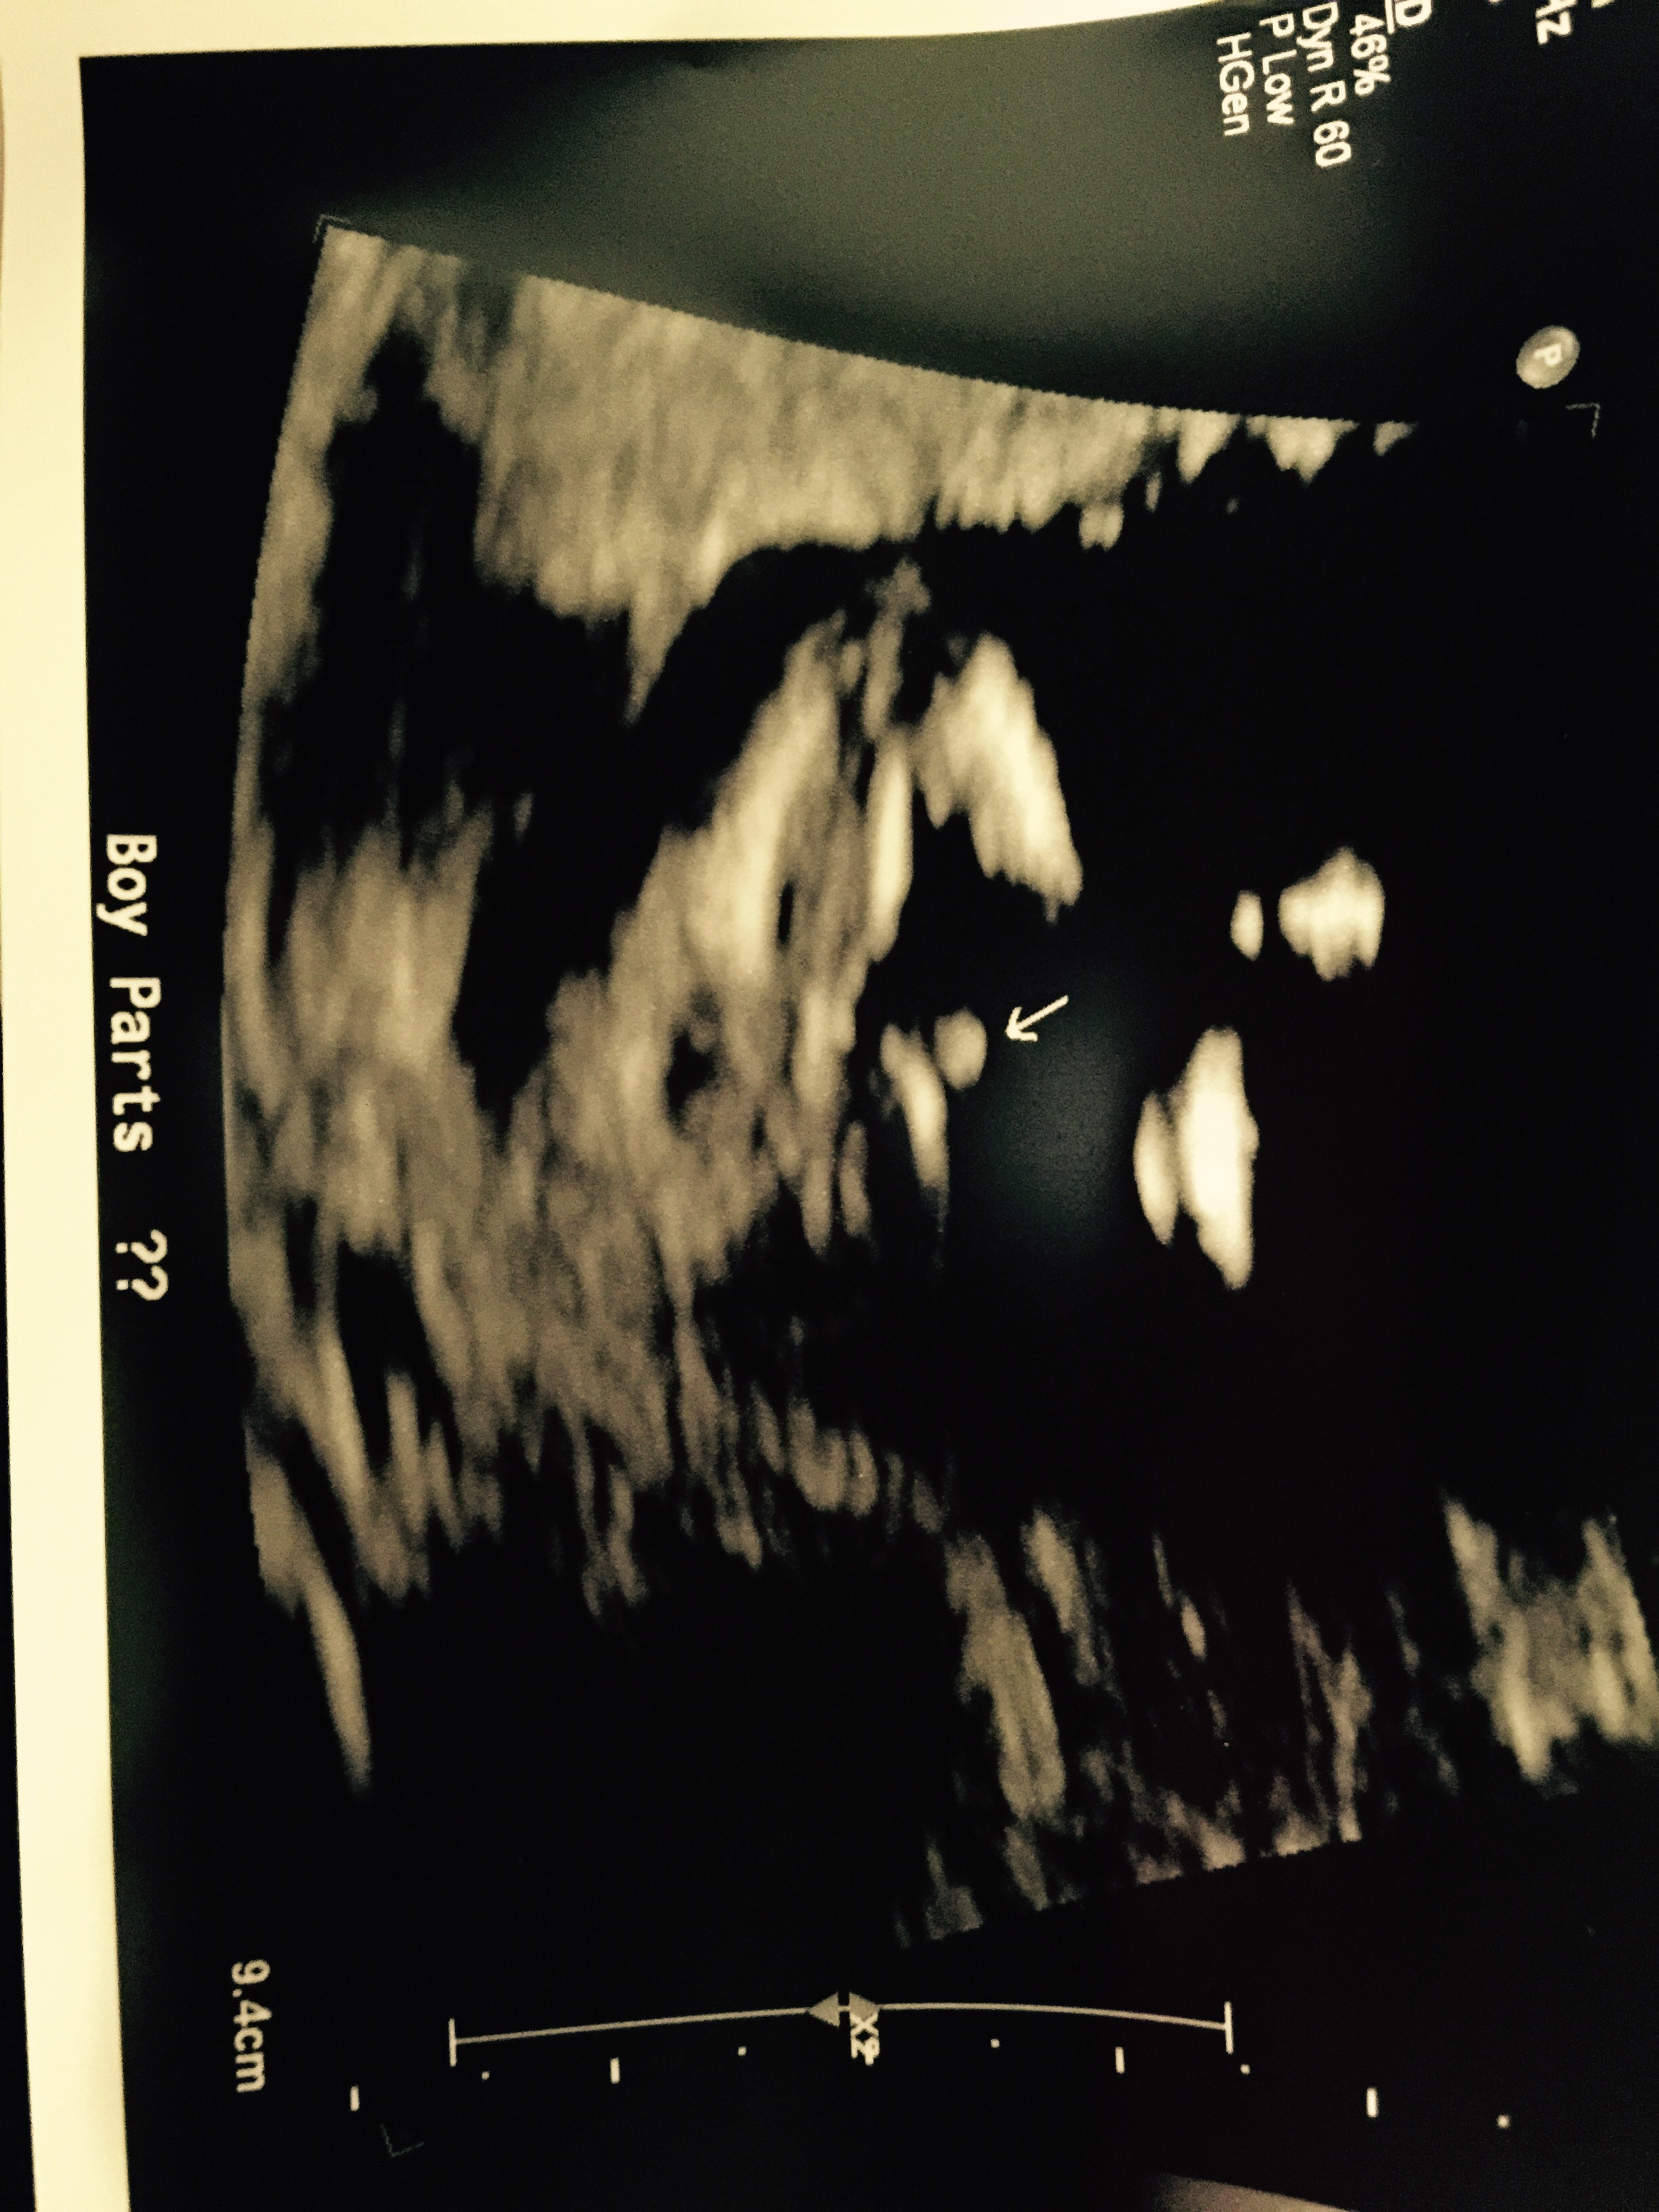

Just got back from my week 15 anatomy scan, sonographer said she was 70% certain it was a boy!!

What do you think?

Looks a lot like a boy! Congrats!

Definitely boy bits, congrats!

Before I get to involved with baby boy names, is there any chance it's genitals are swollen and the baby could be baby pink? Or is it looking all boy? Thanks!!